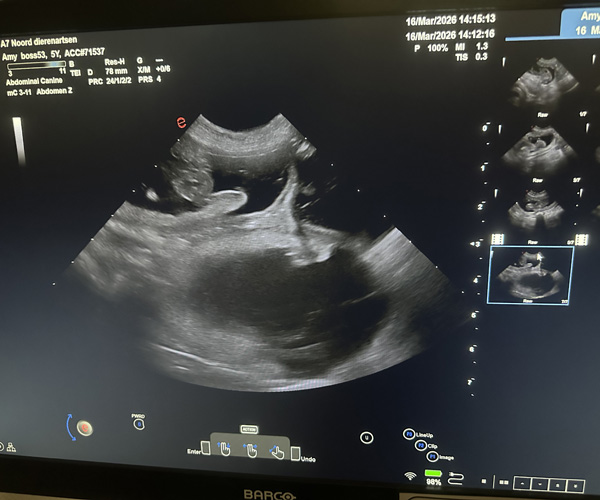

Dinsdag 17 maart: Met heel veel blijdschap delen wij dat onze lieve Amy drachtig is; de echo heeft het bevestigd!

Wij verwachten rond de Paasdagen een prachtig nestje PonDoodle-puppies.

Amy gedroeg zich voorbeeldig bij de dierenarts. Eerst mocht een dierenarts in opleiding de echo doen zodat zij ervaring kon krijgen en daarna deed de dierenarts het nog een keer over. Amy bleef heerlijk rustig liggen en ze genoot van alle aandacht die ze kreeg.